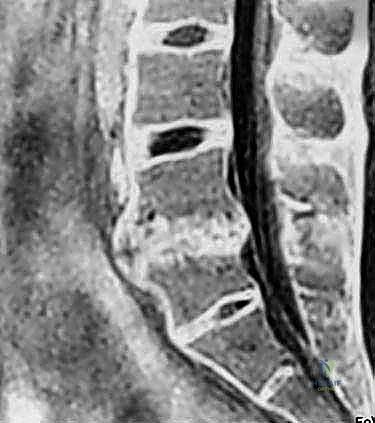

- التصوير بالرنين المغناطيسي (MRI): المعيار الذهبي لتقييم الأنسجة الرخوة. يوضح بدقة حالة الأقراص الفقرية، ودرجة جفافها، ومقدار الضغط على الحبل الشوكي وجذور الأعصاب.

- التصوير المقطعي المحوسب (CT Scan): يقدم تفاصيل دقيقة للغاية عن البنية العظمية، وهو ضروري جداً للتخطيط الجراحي، خاصة في حالات استئصال الجسم الفقري أو وجود تعظم شديد.